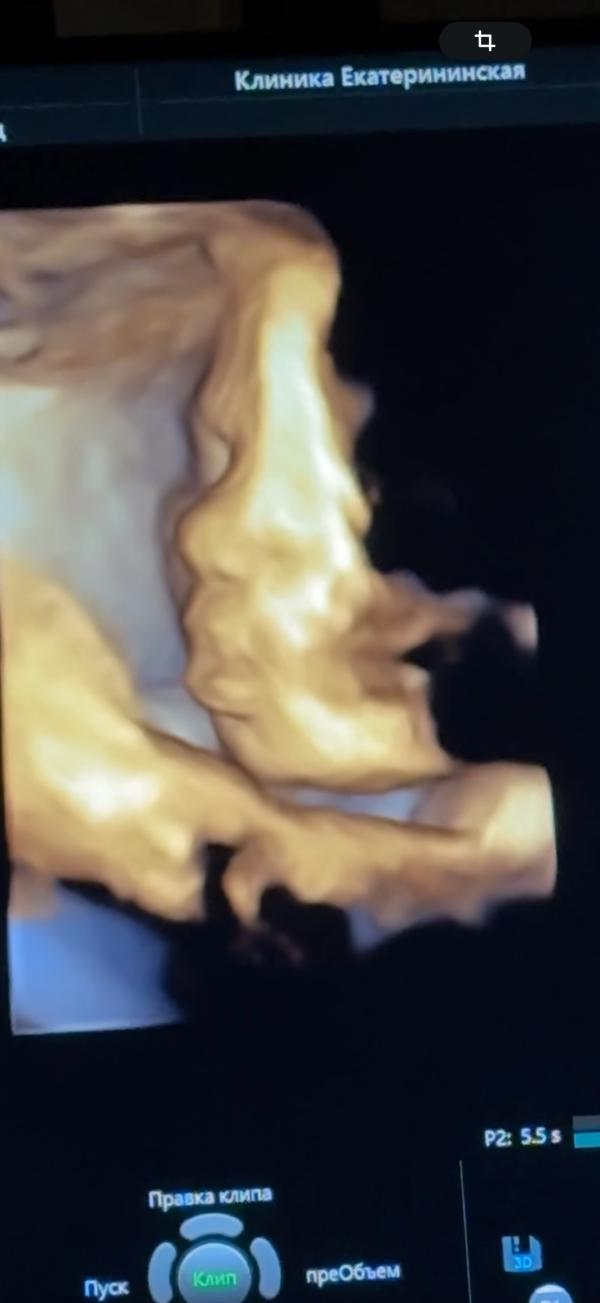

Сегодня прошел третий скрининг🥰 Малышка моя уже 1957 гр, размер соответствует сроку день в день) Умничка моя лежит головкой вниз, обвитий нет. По всей головке уже выросли волосюшки 11 мм, хотя сын и я родились лысыми😅 Теперь так не терпится посмотреть, какая она там получилась🤩 По фото губки пухлее и носик острее чем у сына) Щечки больше, но по размерам меньше сына на этом же сроке)) Шейка длинющая, аж 44 мм🤦🏻♀️ с сыном тоже такая была и родила его я ровно на 41 неделе, не хочу снова так долго ходит😭😅